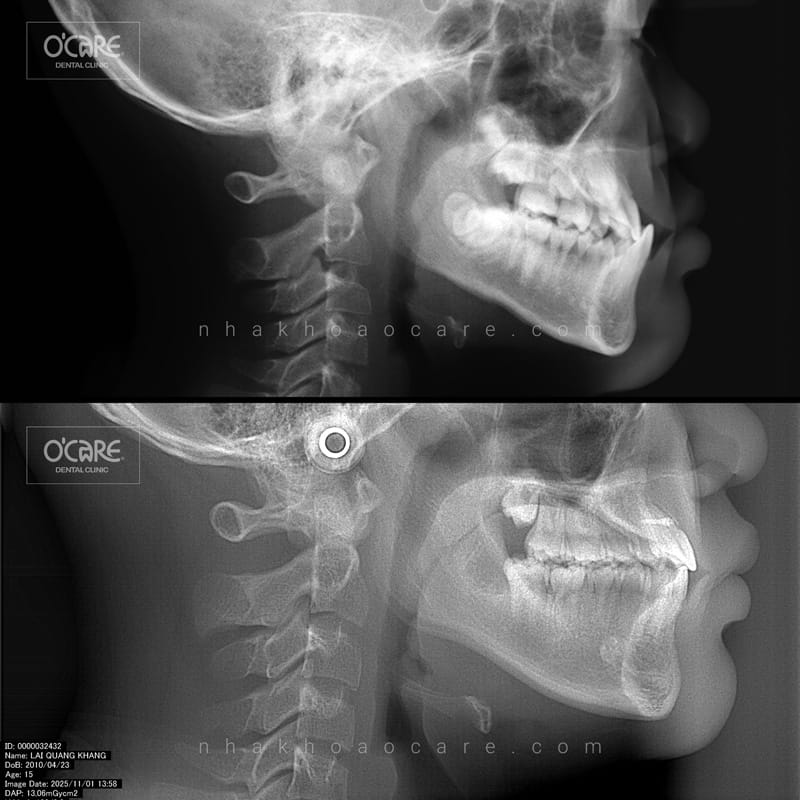

Tại Nha khoa Ocare, chúng tôi vừa hoàn tất thành công một ca niềng răng điều trị khớp cắn ngược cho trẻ em do BS.CKI Lương Thị Lài trực tiếp thực hiện. Kết quả mang lại sự thay đổi rõ rệt về diện mạo và chức năng ăn nhai, giúp bé tự tin hơn trên hành trình trưởng thành.

5. Kết quả sau điều trị khớp cắn ngược tại Nha khoa Ocare

Dưới bàn tay chuyên môn của BS.CKI Lương Thị Lài, các ca niềng răng cắn ngược tại Ocare đều đạt được những kết quả ấn tượng:

- Khớp cắn chuẩn: Hàm trên bao ngoài hàm dưới theo đúng tỷ lệ sinh lý.

- Răng đều đặn: Các răng được sắp xếp đúng vị trí, chuẩn đường giữa.

- Gương mặt hài hòa: Góc nghiêng cải thiện rõ rệt, cằm không còn bị nhô ra phía trước.